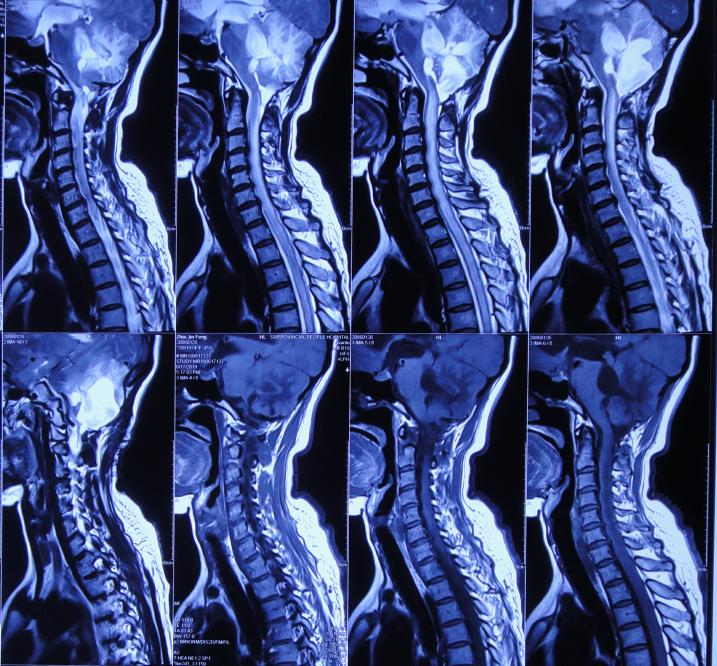

入院治疗17天即2019年7月8日,入院时不能眨眼已变基本正常,头部疼痛较入院时有减轻( 图-22 );查头颅CT示虽有少量硬膜下积液,但脑室基本正常( 图-23 )。

图-22: 2019年7月8日

图-23: 2019年7月8日头颅CT

入院治疗53天即2019年8月13日,进行了脑室腹腔分流术( 图-24 )。

图-24: 2019年8月13日头颅CT

2019年8月23日(李小勇脑脊液科治疗63天)出院,出院时:精神变好,眨眼变正常,入院时睡觉时有尿*禁失**完全消失;颈部,肩部疼痛显著减轻,但走路稍不稳( 图-25 );出院前头颅CT示未见异常( 图-26 )。

图-25: 2019年8月23日

图-26: 出院前头颅CT